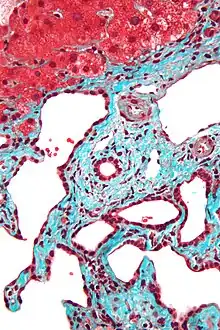

Histopathology of a bile duct hamartoma, high magnification, H&E stain. It shows typical features of bile duct hamartoma: Small to medium sized, irregularly shaped bile ducts lined by bland cuboidal epithelium (may also be flattened). Prominent intervening collagenous stroma. Bile ducts containing eosinophilic debris (may also contain inspissated bile)

Micrograph of a bile duct hamartoma. Trichrome stain. Intermediate magnification